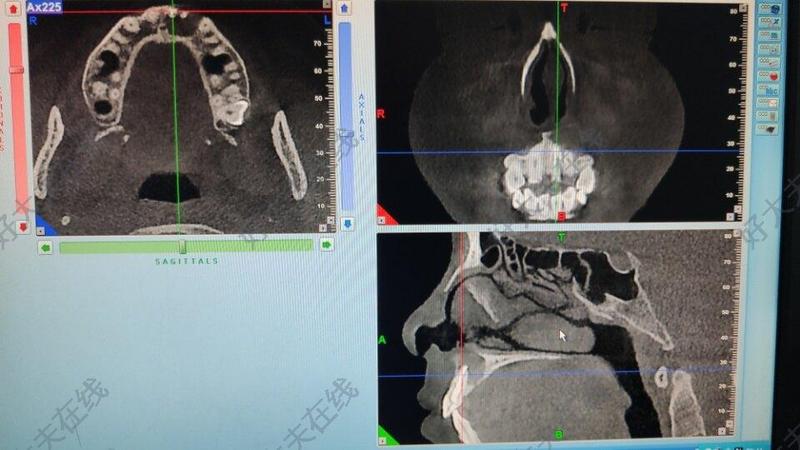

下頜腫瘤切除重建種牙

治療前下頜骨成釉細(xì)胞瘤截骨植骨種牙。該患者成釉細(xì)胞瘤累及下頜骨體部,部分區(qū)域完全沒有正常骨質(zhì),所以不能行保守治療。只能選擇截骨,同時(shí)使用計(jì)算機(jī)設(shè)計(jì)、手術(shù)導(dǎo)板,選用血管化血管化髂骨瓣修復(fù)。骨修復(fù)同期種牙。最終實(shí)現(xiàn)形態(tài)和功能的個(gè)性化重建。治療后治療后272天下頜骨成釉細(xì)胞瘤截骨植骨種牙。該患者成釉細(xì)胞瘤累及下頜骨體部,部分區(qū)域完全沒有正常骨質(zhì),所以不能行保守治療。只能選擇截骨,同時(shí)使用計(jì)算機(jī)設(shè)計(jì)、手術(shù)導(dǎo)板,選用血管化血管化髂骨瓣修復(fù)。骨修復(fù)同期種牙。最終實(shí)現(xiàn)形態(tài)和功能的個(gè)性化重建。

單小峰醫(yī)生的科普號(hào)2020年03月19日1359